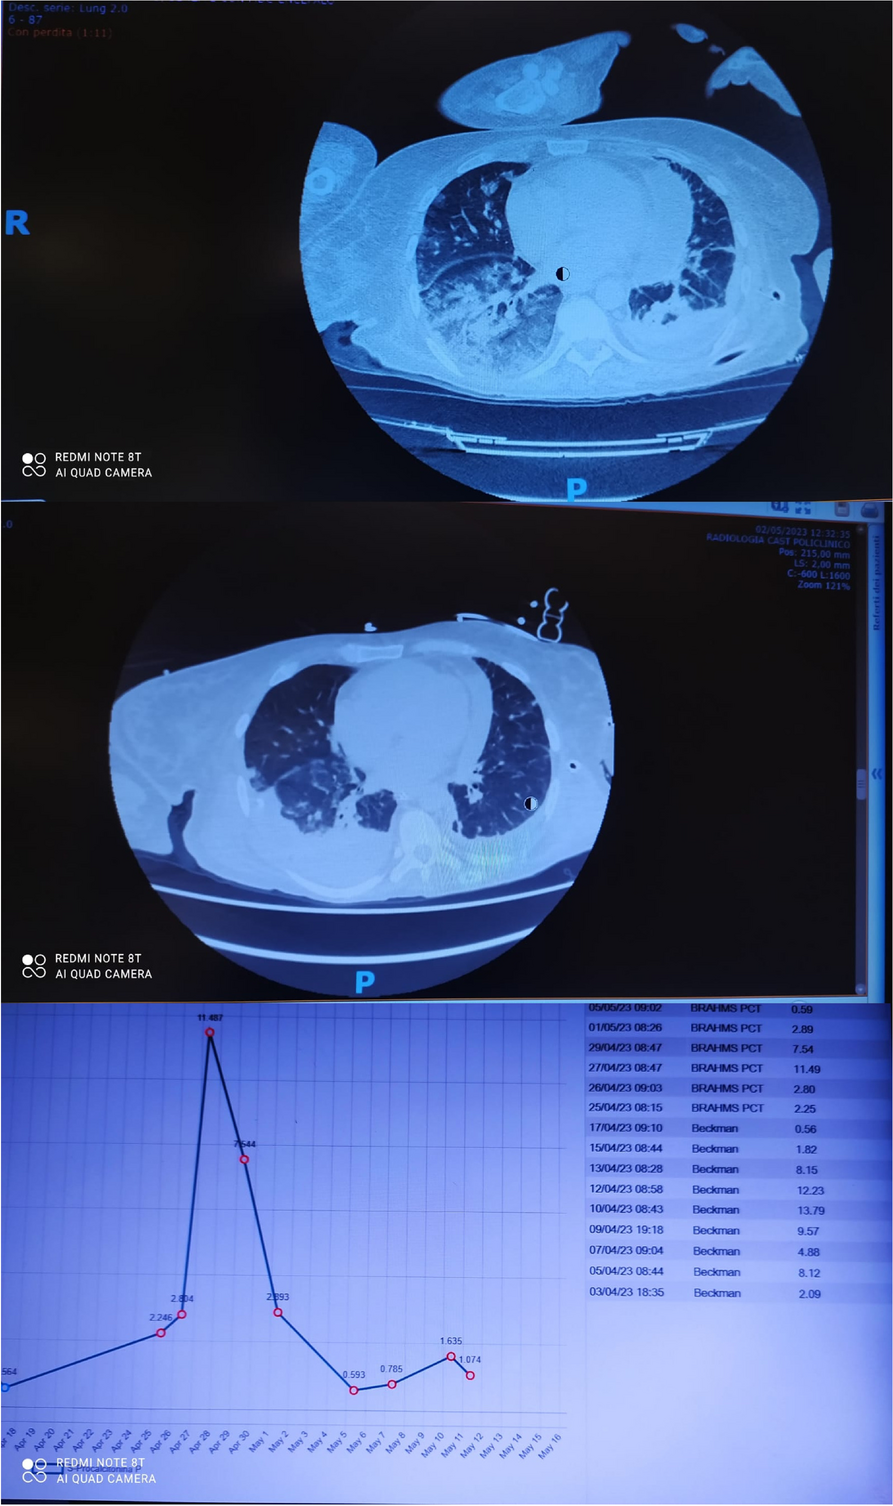

In this specific case, the patient, affected by L. Pneumophila, presented a PO2/FiO2 ratio between 100mmHg and 200mmHg, giving rise to a moderate ARDS panel according to Berlin Criteria (Image 1).

For this reason, we decided to use a non-invasive periprocedural ventilation mode, specifically the High Flow Nasal Cannula (HFNC), to reduce the risk of postoperative pulmonary complications due to invasive ventilation through endotracheal intubation (ETI).

Image 1 (abstract A9).

See text for description